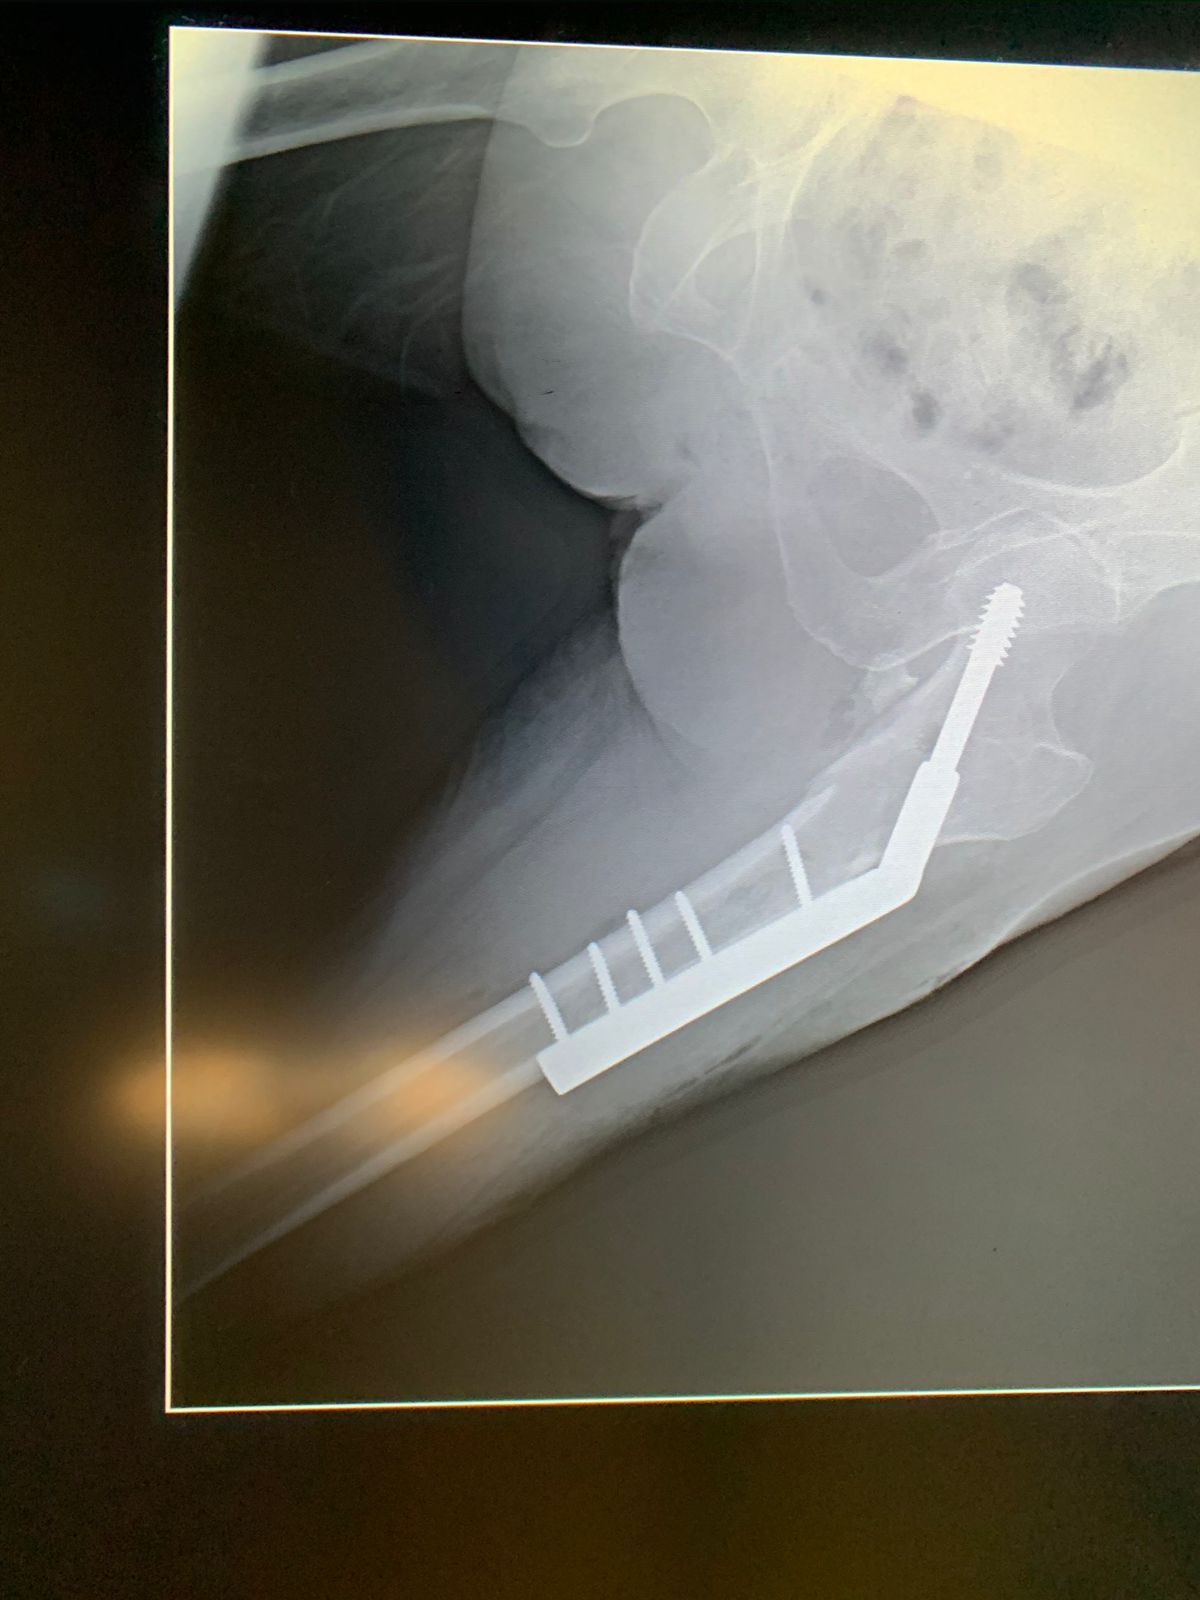

• Reemplazo articular de cadera

Reducción ortopédica e inmovilización de fracturas y/o luxaciones

Algunas lesiones por fracturas, esguinces o luxaciones, pueden tratarse de forma conservadora, es decir, con la aplicación de yesos o férulas de fibra de vidrio. Para poder determinar el manejo conservador debemos tomar proyecciones radiograficas e incluso tomografías para hacer un mejor abordaje y ofrecerte el mejor tratamiento